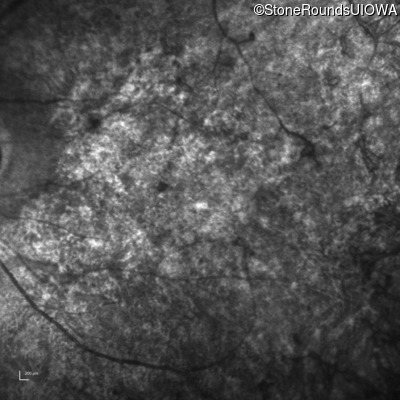

Infrared Fundus Photograph - Right - 20/200 sc

Exemplar